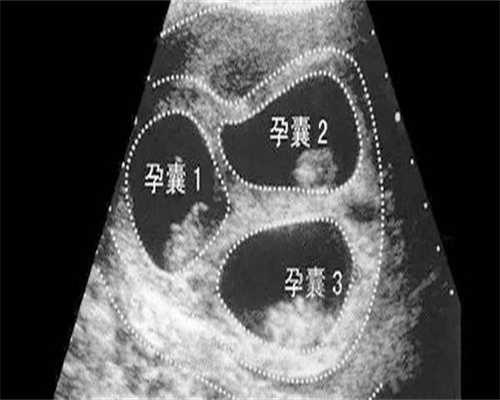

试管婴儿三代技术的优势在于双胞胎的出生率更高;细胞减胎可以降低宫外孕和胎儿畸形的可能性;遗传毒性检测可以有效避免遗传性疾病的出现,让孩子的健康得到更好的保障。